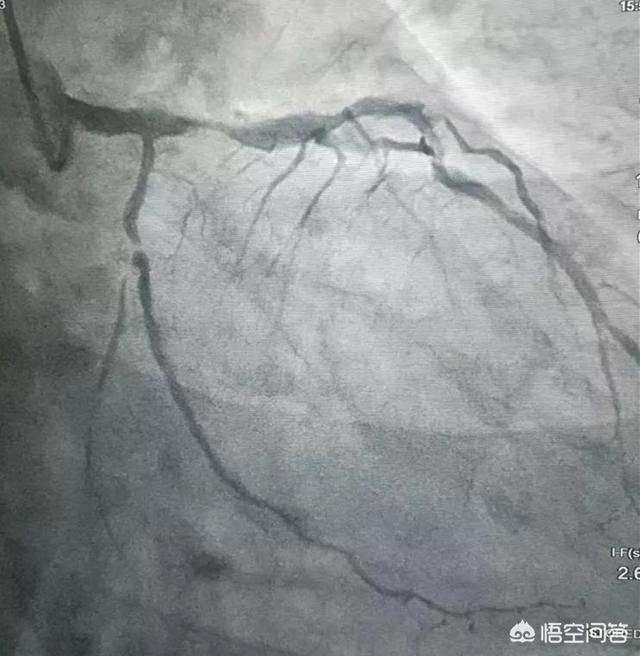

心臓ステントは冠動脈ステントとも呼ばれ、PTCA(経皮経管冠動脈形成術)手技で使用される器具である。心臓ステントは、体外では小さなメッシュ壁の金属チューブのように見え、ワイヤーとその前部のマイクロカプセルなどで構成されています。動脈ステントは動脈を支え、狭窄を解消し、スムーズな血流を確保する役割を継続的に果たすことができる。ステントは一般に急性心筋梗塞やその他の急性冠症候群の治療に用いられ、患者の生命を救ったり、生活の質を向上させたりする。

心臓ステント手術は、まず人の腕や脚の動脈から小さな開口部を開け、小さな弾丸のようなものが装填されたプローブを挿入したラインに接続し、小さな弾丸の超音波観察を通して、弾丸の後に閉塞した場所の冠動脈血管に到達し、鉄の傘である弾丸を開くと、突然血管をサポートするために血管が一時的に支えられているので、血液が上に来ることができます。